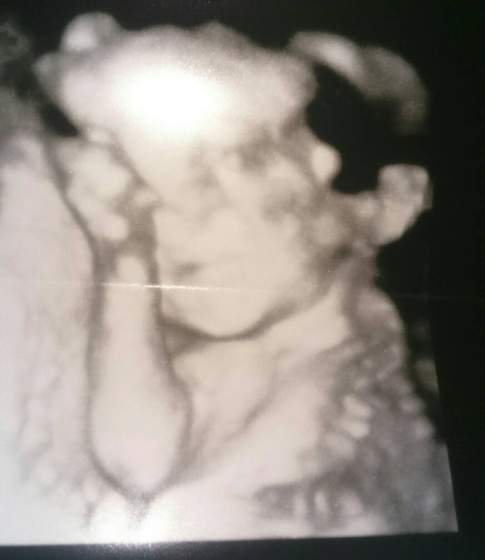

Ja już po wizycie naszczescie z szyjka wszystko dobrze.

Nasze maleństwo ma 450gram i wszystko jest na swoim miejscu :-)

Co do mojego brzucha lekarz kazał leżeć bo mała jest bardzo nisko, przepisał nospe i luteine dostałam też skierowanie na glukozę.

A na koniec uśmiech Lenki :-* <3